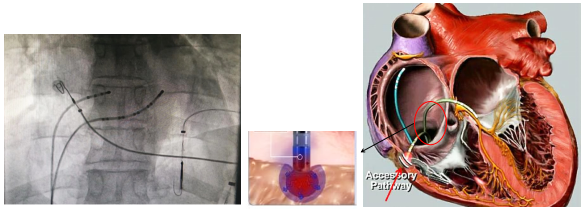

射频消融术是一种介入技术,是使用电极导管在心脏腔的某一部分来释放射频电流,导致局部心内膜和心内膜下心肌的凝固性的坏死,从而破坏某些快速心律失常的起源点。三维射频消融术是使用特殊的一种导管在患者心脏内移动时,在磁场或者电场中来显示,从而引导和帮助判断导管的位置。它的精确度是高于x光透视的检查,这样有助于定位导管位置和找到焦点。创伤小痛苦少,对心肌的损伤非常有限,不会对心脏功能产生影响。是治疗快速性心律失常非常有效方法。